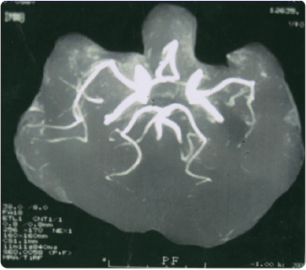

MRAによる脳の血管画像

来院時

精密検査を行ったところ、MRAによって、 左中大脳動脈の末梢血管がほとんど見えない 状態であることがわかりました。